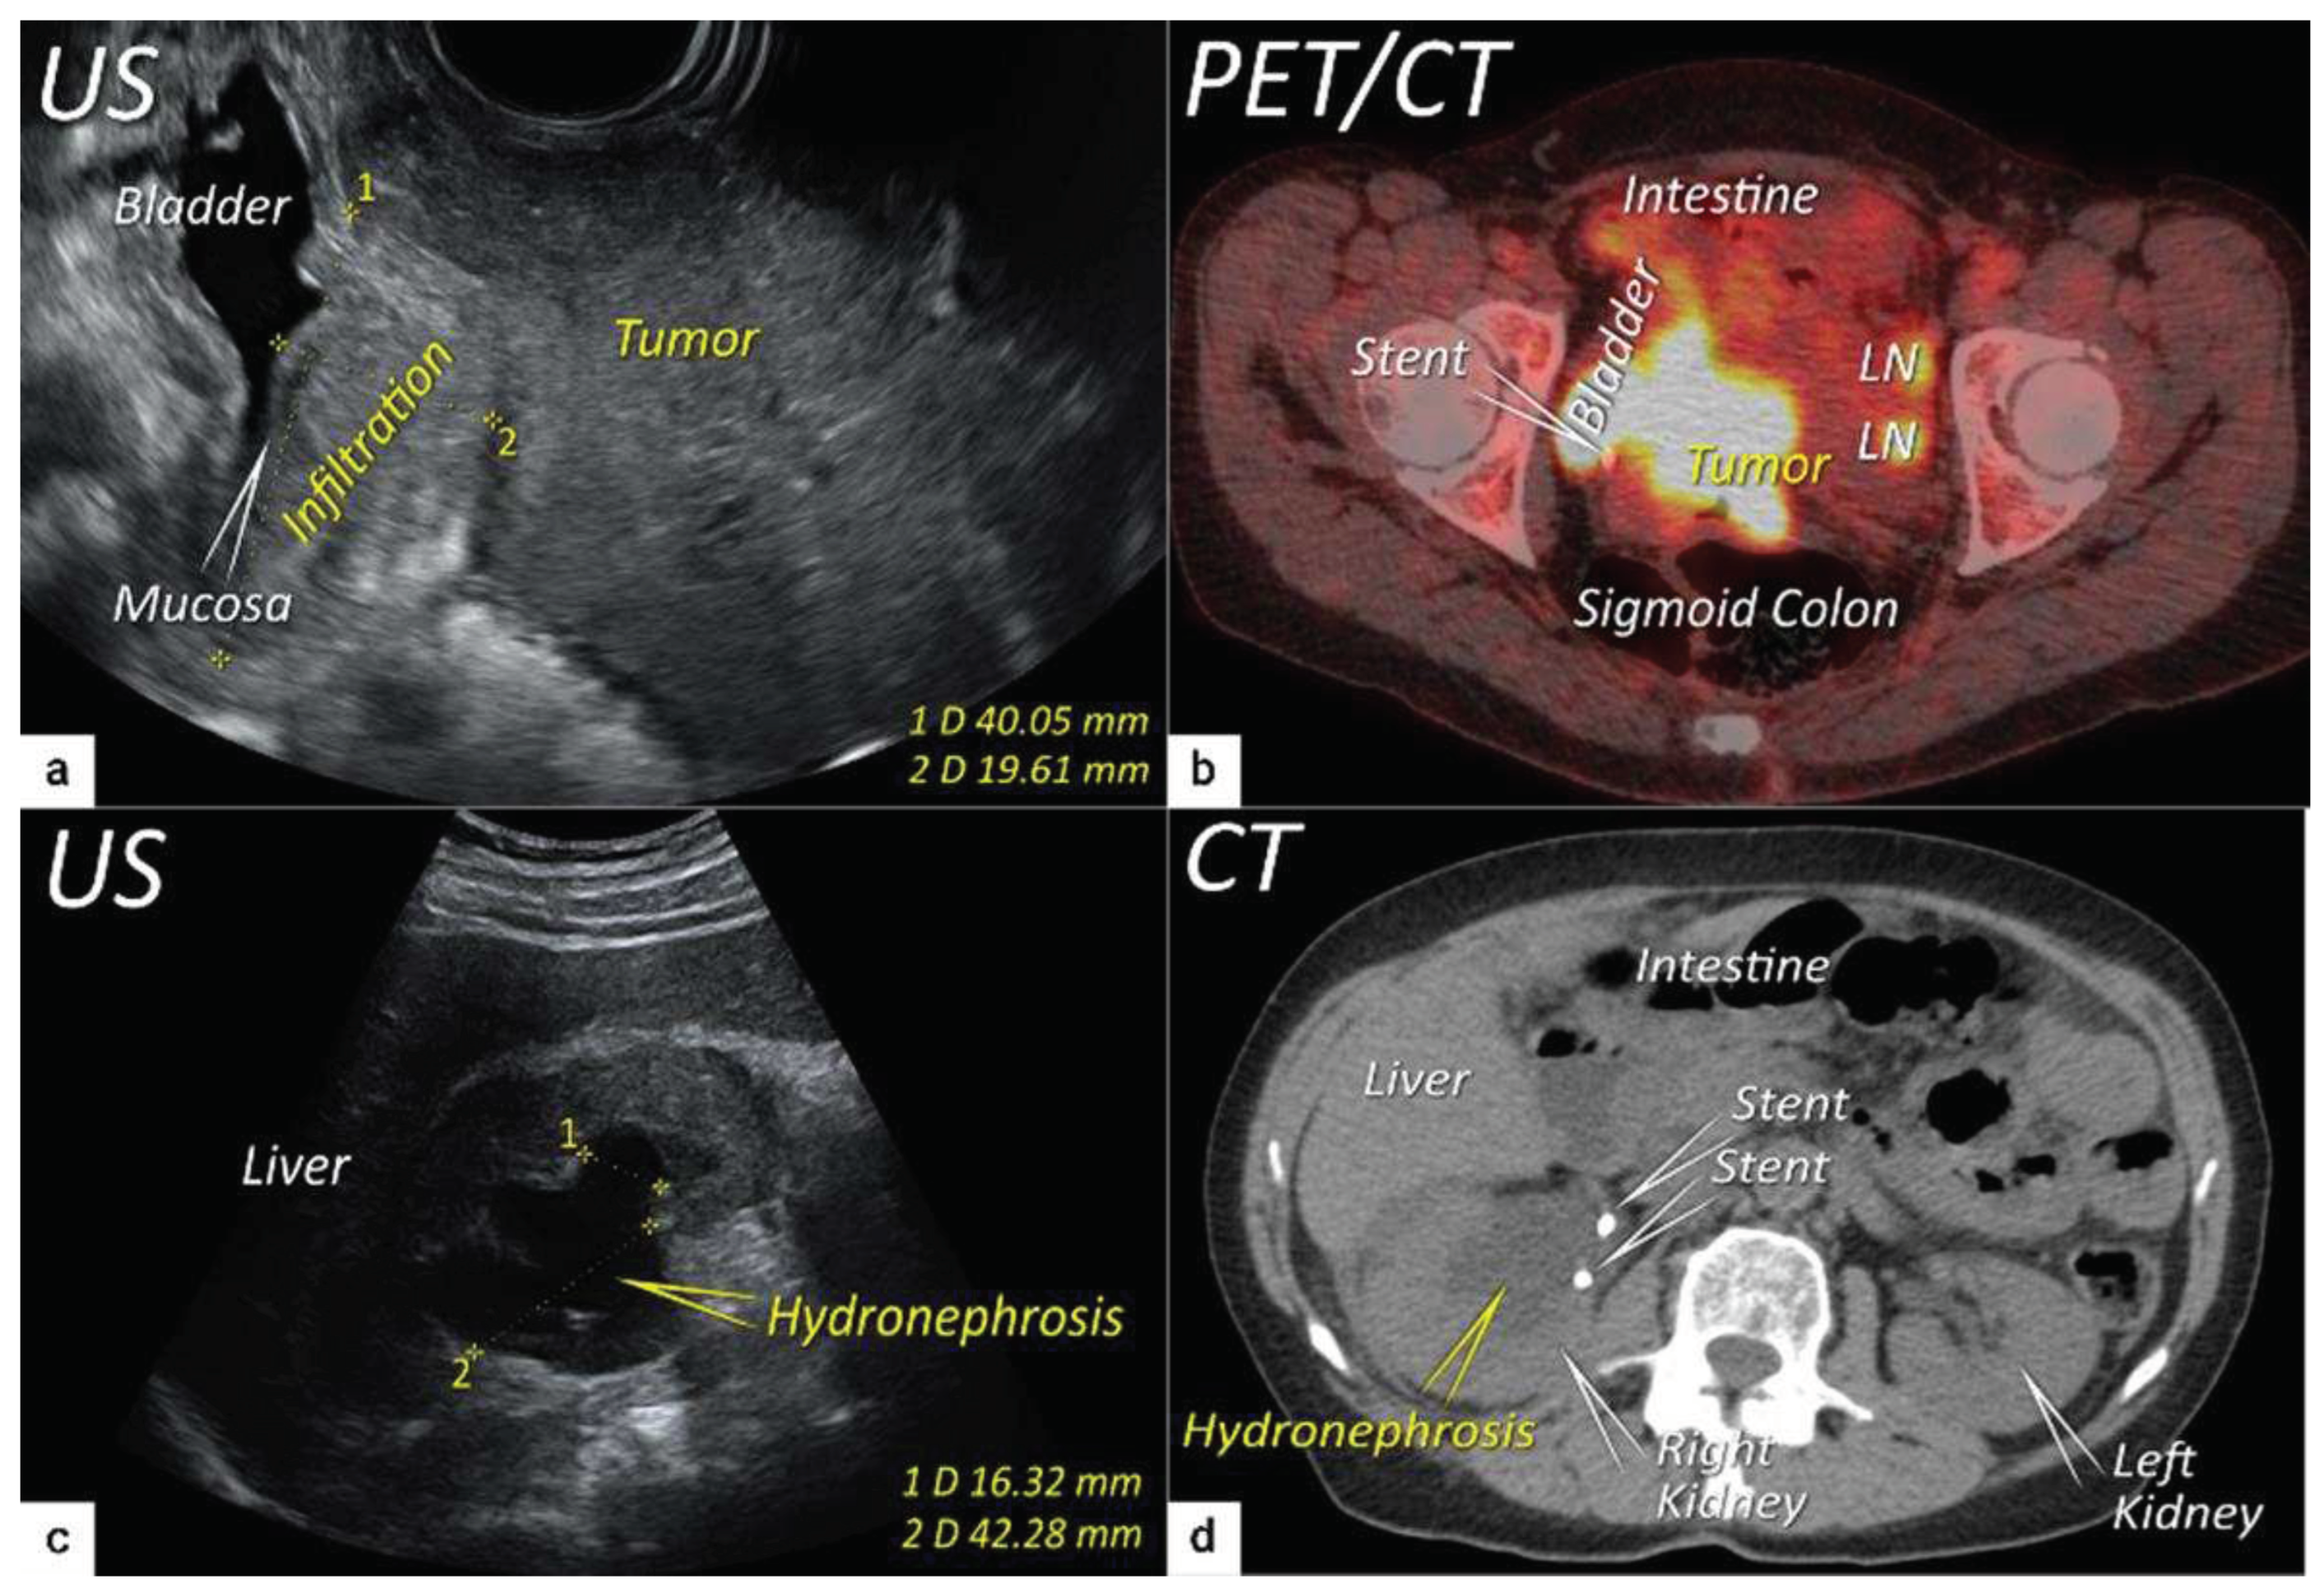

| T3e | IIIe | Carcinoma involves the lower third of the vagina and/or extends to the pelvic side wall and/or causes hydronephrosis or non-functioning kidney | Tumour infiltration of the lower third of vagina or lateral pelvic side wall. Pelvic side wall infiltration is considered when the tumour causes hydroureter, infiltrates the obturator internus, piriformis, and levator ani muscles, encases the iliac vessels, or invades the pelvic bones on US or MRI. |

| T3b | IIIB | Tumour extension to the pelvic side wall and/or hydronephrosis or non-functioning kidney (unless known to be due to other cause). | US: Hypoechogenic tumor projections up to pelvic side wall +/- infiltration of iliac vessels, ureters, muscles, presence of hydronephrosis MRI: Hyperintense infiltration up to the pelvic side wall, loss of normal parametrial signal intensity and increased signal intensity in pelvic musculature due to tumour invasion seen on T2W-images. |

| T4f | IVAf | Tumour invasion into the mucosa of the bladder or rectum (biopsy-proven) or into adjacent organs. | US: Negative sliding sign, hypoechogenic tumour infiltration of bladder / rectal wall up to echogenic mucosa with polypoid tumor seen intraluminally. MRI: Focal or diffuse disruption of the normal T2-low signal intensity wall of the bladder/rectum, irregular or nodular wall, sometimes including an intraluminal tumour mass. Bulous edema sign, which is hyperintense thickening of the bladder mucosa on T2W images, is only an indirect sign of invasion and should not be regarded as T4 unless confirmed mucosal infiltration at cystoscopy. Infiltration of the posterior bladder wall without mucosal infiltration should not be regarded as T4a. |